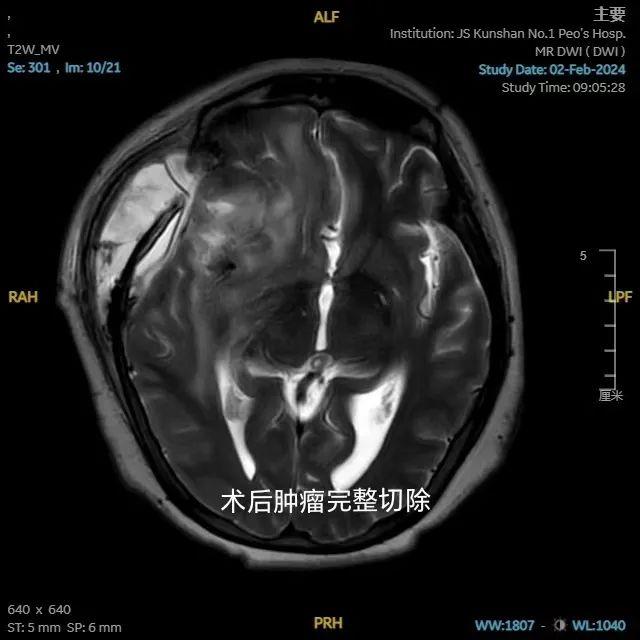

官女士,60歲,2年前無明顯原因出現(xiàn)頭痛,近期加重,到昆山市一醫(yī)院神經(jīng)外科就診,磁共振(MRI)示:右側(cè)額葉見一類圓形異常信號腫塊影,大小約46*46*51mm,邊界清晰、光整,周圍大片水腫。立即安排住院治療。神經(jīng)外科張曙光主任團(tuán)隊(duì)經(jīng)過術(shù)前充分評估,經(jīng)過近5小時(shí)手術(shù),完整的保護(hù)了后大腦中動脈并順利切除腫瘤,切除腫瘤后立即在手術(shù)室完成術(shù)中CT掃描,未見明顯異常,送回病房,官女士現(xiàn)已康復(fù)出院。